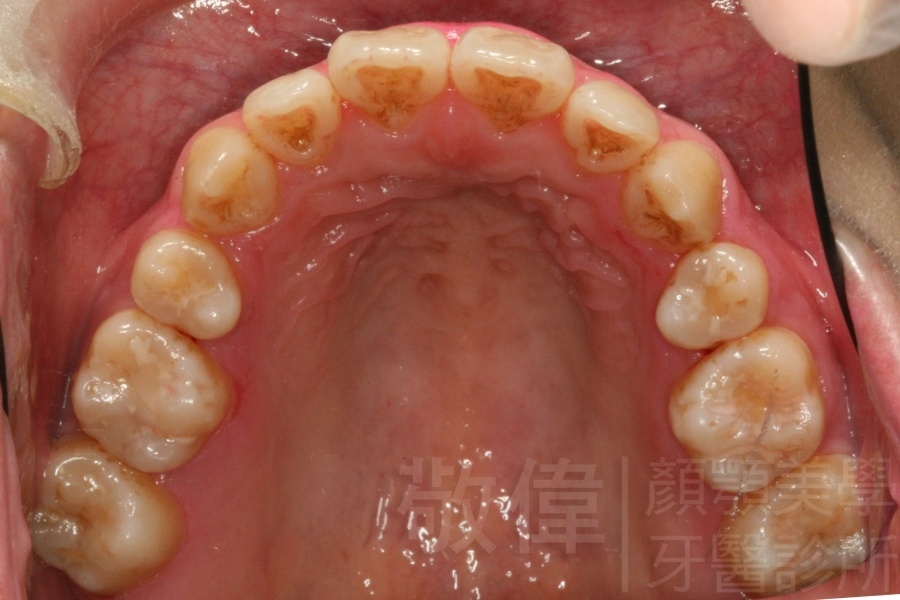

變臉矯正,原來戽斗妹跟大歪臉變成自信正妹

經由本院3D數影X光影像儀分析、與3D齒顎顏矯正技術,再配合口腔顎面正顎專科醫師施以正顎手術治療,雙方共同合作,使患者臉部外觀有很好的改善,大歪變小歪,產生了天南地北的大改變,她的人生也整個變得不一樣。

因為矯正與正顎手術的配合,使「戽斗妹」變成了「陽光正妹」,完全的改變了她的人生,在面對各種場合、與人交際都散發出自信微笑。所以,奉勸家長,如果小朋友有臉顎畸型的問題,應該考慮配合做這種簡單、安全、有效的正顎手術。